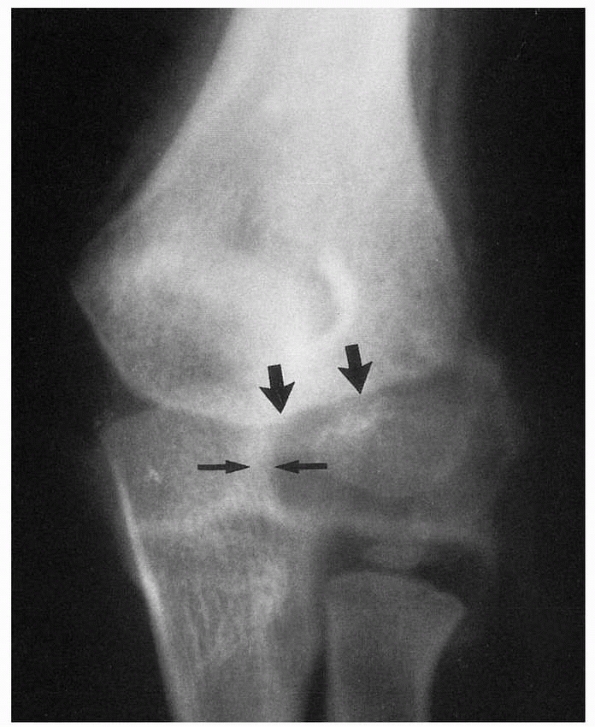

![]() |

FIGURE 15-1 A. Injury film of a 7-year-old with an undisplaced fracture of the lateral condyle (small arrows). Attention was drawn to the location of the fracture because of extensive soft tissue swelling on the lateral aspect (white arrows). B.

Because of the extensive soft tissue injury, there was little intrinsic stability, allowing the fracture to become displaced at 7 days (arrow). |